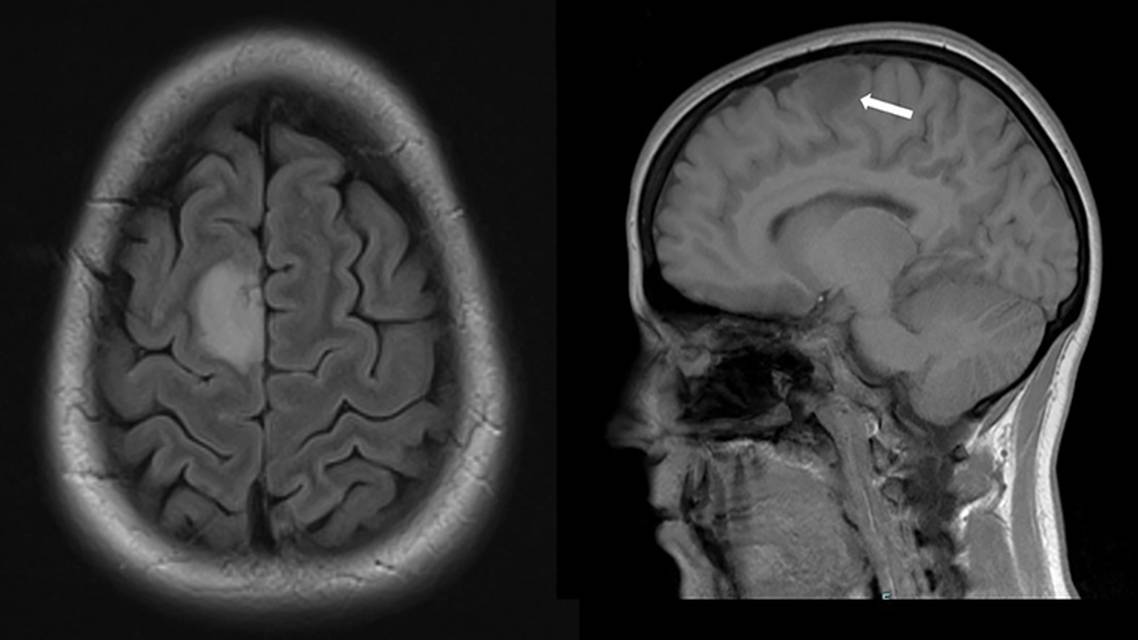

Further evaluation revealed that RP had no known seizure history and no identifiable risk factors for epilepsy. RP had never experienced a seizure without a music trigger. Neurologic examination was unremarkable and did not reveal deficits. There were no significant findings from laboratory testing. EEG results were normal despite several attempts to trigger the symptoms by singing and listening to songs that had triggered episodes previously. A MRI brain scan was notable for a 2.9-cm nonenhancing T2-hyperintense lesion in the right superior frontal gyrus that was concerning for a low-grade glioma. Gross total resection of the mass revealed a grade 2 oligodendroglioma (Figure).